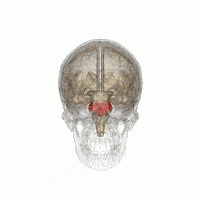

边缘系统(The limbic System)

大脑的边缘系统在脑干上,就是它让人类如此疯狂。

边缘系统是一种生存系统。如果你在做动物也会做的事情,可能就是你的大脑边缘系统在驾驭你。

无论你喜欢与否,你做的那些事情,就是处在原始的生存模式。

边缘系统也是你的情感所在,最终,情绪也都是为了生存——情感是更高级的生存机制,对于处在一个复杂的社会结构中的动物是必须的。

每当你发生思想斗争时,你的边缘系统很可能会让你做出你会后悔的事情。